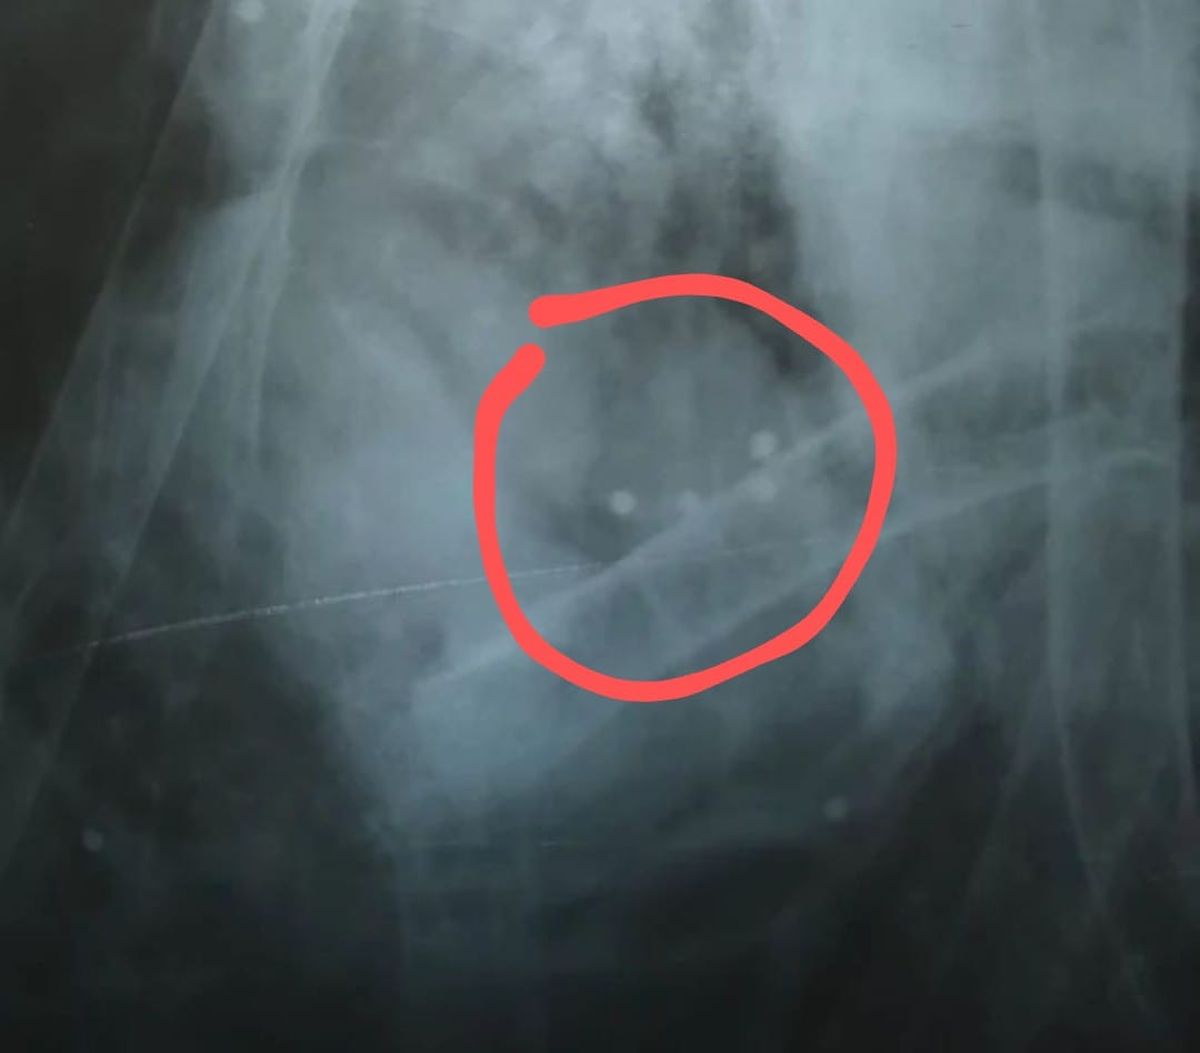

Según los especialistas de la fundación, el ave tenía 11 perdigonazos, lo que le produjo una hemorragia interna, la ruptura de su hígado y otras lesiones.

Los profesionales de la Fundación Cullunche publicaron en su perfil de Instagram las fotos de la autopsia, y manifestaron que "no queremos imaginarnos el sufrimiento de este magnífico e imponente animal que pesaba 14 kilos”.